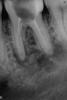

mitya_mitya Опубликовано 17 июля, 2011 Поделиться Опубликовано 17 июля, 2011 Лечу зуб (предпоследний нижний) уже около месяца. Сначала сильно опухла десна, сделали разрез - гноя не было. Поставили дренаж и назначали антибиотики. Прпухлость спала но не до конца. Затем открыли зуб, распломбировали каналы (по словам врача- вышли во всех трех за верхушку корнч) положили какую белую пасту, закрыли временной пломбой. Вечером началась аддская боль не помогали обезболивающие, сам выташил временную пломбу боль прошла. Из зуба продолжало попахивать гнильцой. Начал пить ибупрофен, еще раз почистили каналы и положили что то типа формалин-резорциновую смесь на ватке и закрыли зуб временной пломбой. Болей не было но на десне осталась более меньшая припухлость достаточно твердая, но не болезненная. Через 5-6 дней открыли зуб, запах не было никакого, чуствительность при надавливании и ощущение выросшего зуба тоже пропали. Продолжаю пить ибупрофен тавегил и теперь еще добавили амоксиклав. Сейчас зуб открыт, полощу его стоматофитом.Вопрос в следующем - правильно ли на ваш взгляд проводитьсч лечение и что вы могли посоветовать.Заранее спасибо.Припухлость на десне примерно 1,5 см визуально не видно, только на ощупь.Снимок сделал сегодня. Ссылка на комментарий